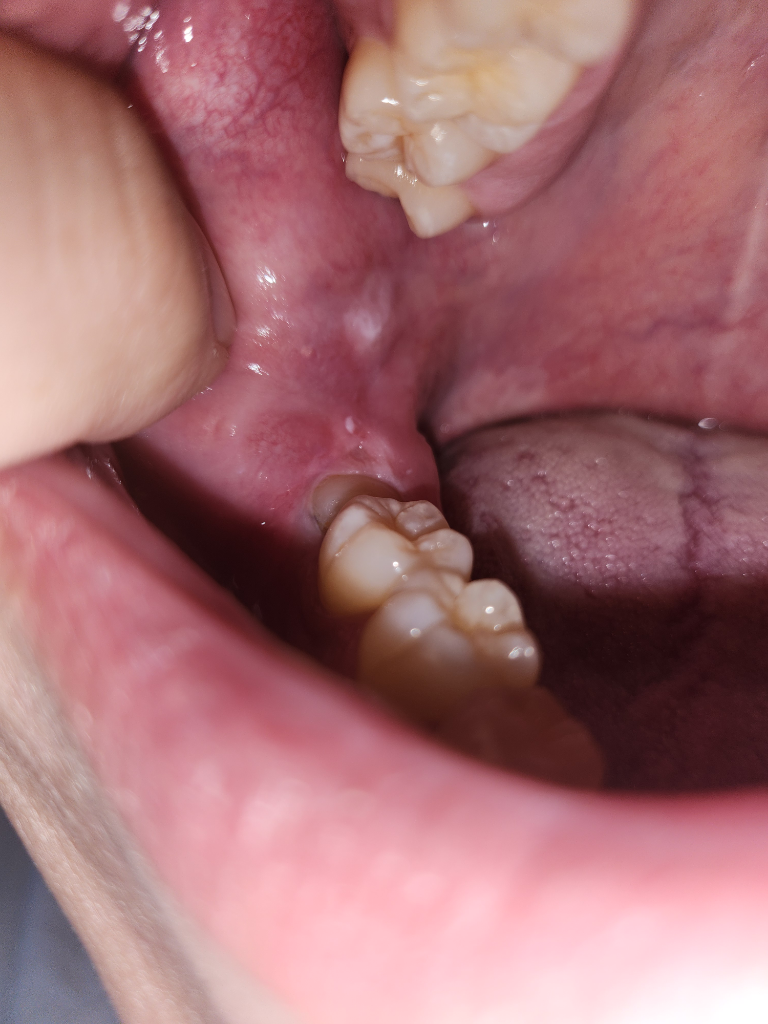

아마 볼살이 치아에 씹히면서 생긴 자국같습니다. 크게 문제가 잇는건 아니니 너무 걱정하지 않으셔도 됩니다.

구강암일 가능성은 낮으며, 구내염일 가능성이 높아 보입니다. 소독을 위해 헥사메딘 가글이나 탄툼가글로 해당부위를 충분히 가글하길 권하며, 충분한 휴식과 영양섭취를 권합니다.